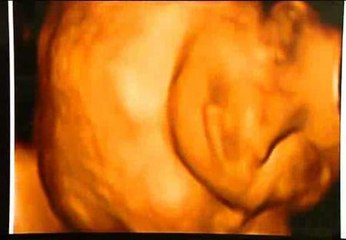

Óliver, el pequeño que debe ser operado de un tumor cerebral, ya se encuentra ingresado en el hospital de Barcelona

El menor llegaba junto a su madre desde México en un avión medicalizado ofrecido por un empresario anónimo